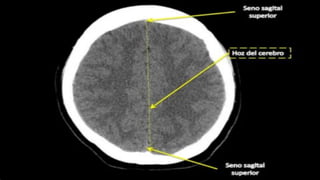

Infección

Tomografía

computarizada craneal

sin contraste. Cortes

axiales